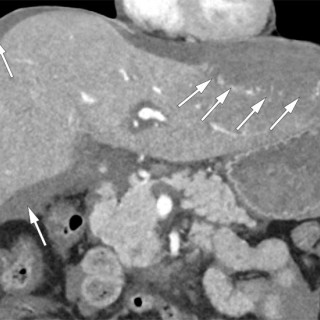

Kasuistikken beskriver en pasient med cystisk ekinokokkose og behov for omfattende kirurgisk behandling. Tilstanden er sjelden i Norge, men utgjør et betydelig folkehelseproblem globalt. På grunn av økende innvandring fra høyendemiske land, bør norske leger kjenne til denne zoonosen. En tidligere frisk mann i 40-årene, oppvokst i Midtøsten og bosatt i Norge de siste årene, ble akutt innlagt på medisinsk avdeling ved lokalsykehuset, etter to døgn med respirasjonsavhengige smerter i høyre hemitoraks. I forkant av innleggelsen hadde han hatt fem ukers sykehistorie med høyresidige flankesmerter...